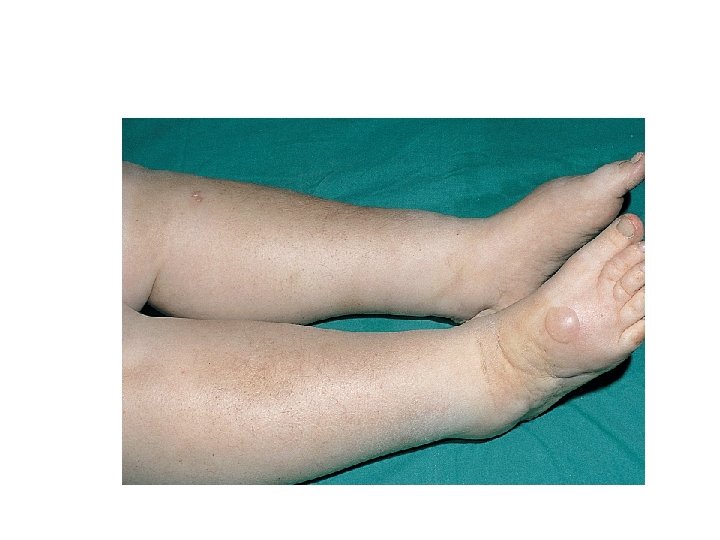

Components of nephrotic syndrome Proteinuria 3. 5 g/24 hr/1. 73 m 2 Hypoalbum. ( serum alb<3. 5 g/d) Hypercholesterolemia (>200 mg/dl) Peripheral edema ± anasarca

Acute Complications of Nephrotic Syn. peripheral edema, ascites, and effusions increased risk for infection (especially cellulitis and, in 2 to 6%, spontaneous bacterial peritonitis); anemia; abnormal thyroid function; Thromboembolism (especially renal vein thrombosis and pulmonary embolism in up to 5% of children and 40% of adults). Thromboembolism may develop not only because of urinary loss of antithrombin III but also because of increased hepatic synthesis of clotting factors, platelet abnormalities, and hyperviscosity from hypovolemia.

Symptoms and Signs anorexia, malaise, and frothy urine caused by high concentrations of protein. Edema may cause dyspnea (pleural effusion or laryngeal edema), chest discomfort (pericardial effusion), arthralgia (hydrarthrosis), abdominal pain (ascites or, in children, mesenteric edema). Edema may obscure signs of muscle wasting and cause parallel white lines in fingernail beds (Muehrcke's lines).